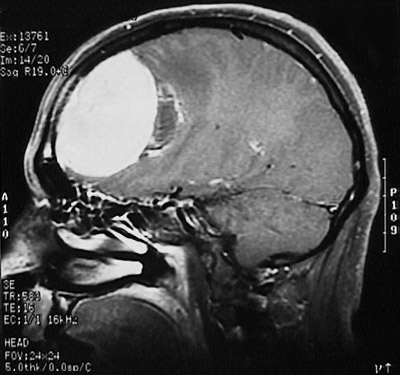

| This enhanced MRI scan in sagittal view demonstrates bright enhancement of a large meningioma in the parasagittal region. CNS neoplasms often enhance with contrast agents such as gadolinium. Despite the size, this tumor is amenable to surgical resection with minimal sequelae. |